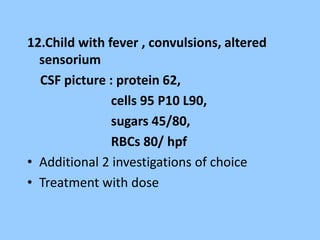

1. The document discusses EEG patterns and findings in various neurological conditions seen in children. It includes descriptions of normal EEG findings as well as abnormal patterns seen in conditions like absence seizures, West syndrome, benign childhood epilepsy with centrotemporal spikes, Lennox-Gastaut syndrome, non-convulsive status epilepticus, subacute sclerosing panencephalitis, and herpes encephalitis.

2. Case studies are presented with clinical histories and EEG findings to illustrate different pathologies. Treatment options are also mentioned for many of the conditions.